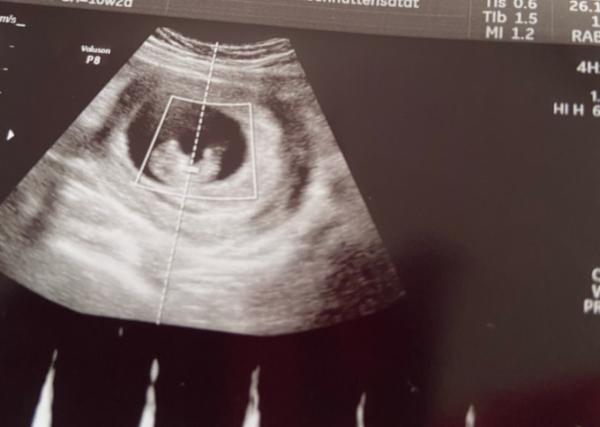

Heute wegen Blutungen in der Notaufnahme gewesen ( ist aber alles super ) Ist gewachsen hüpft rum, Herzchen schlägt kräftig Das Bild was hier angeheftet is vaginal. Unten in den Kommentaren mach ich Bauch noch

Laut Periode 10+2 laut Baby 9+5